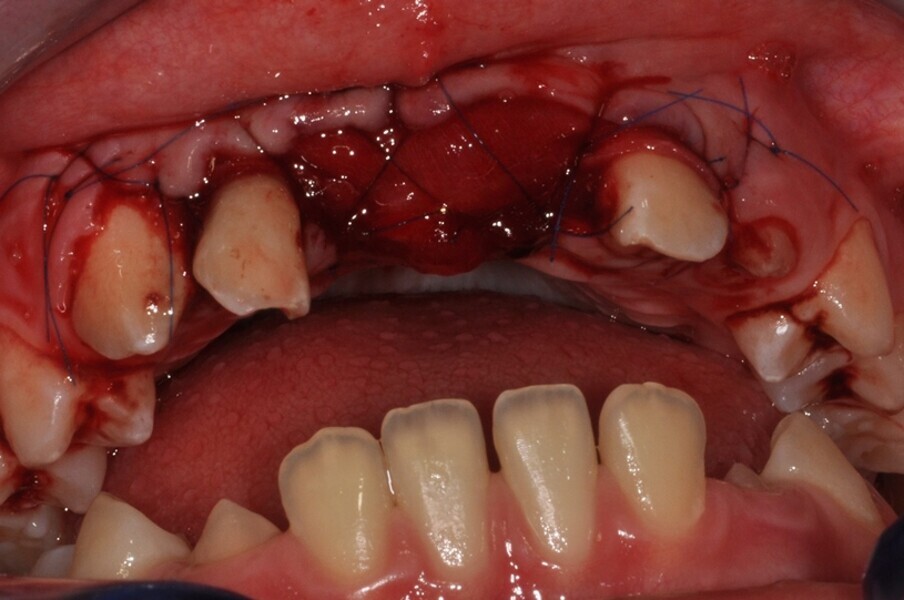

Ryc. 9_Miejsce biorcze po wytworzeniu łoża.